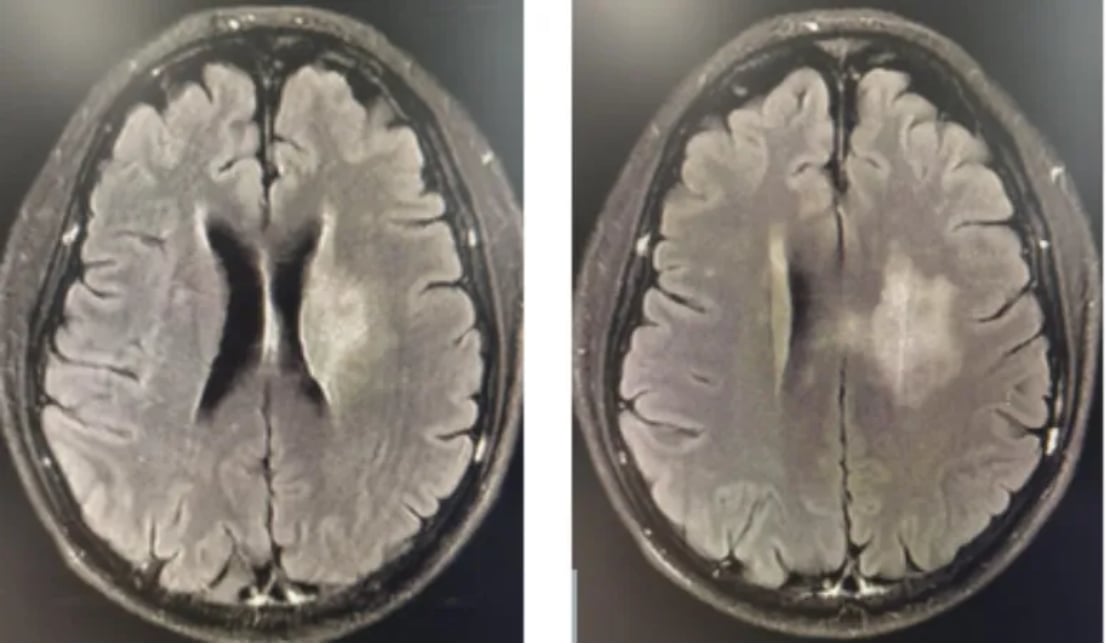

图1 初诊影像学

图2 首次治疗后复查影像学